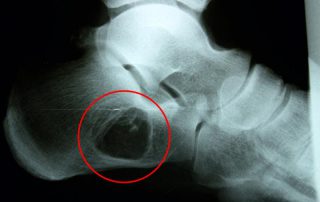

Cysta kości piętowej – pacjent 50 lat

Pacjent lat 50 zgłosił się z nawracającymi bólami w stopie. Po diagnostyce okazało się, że powodem jest cysta kości piętowej.